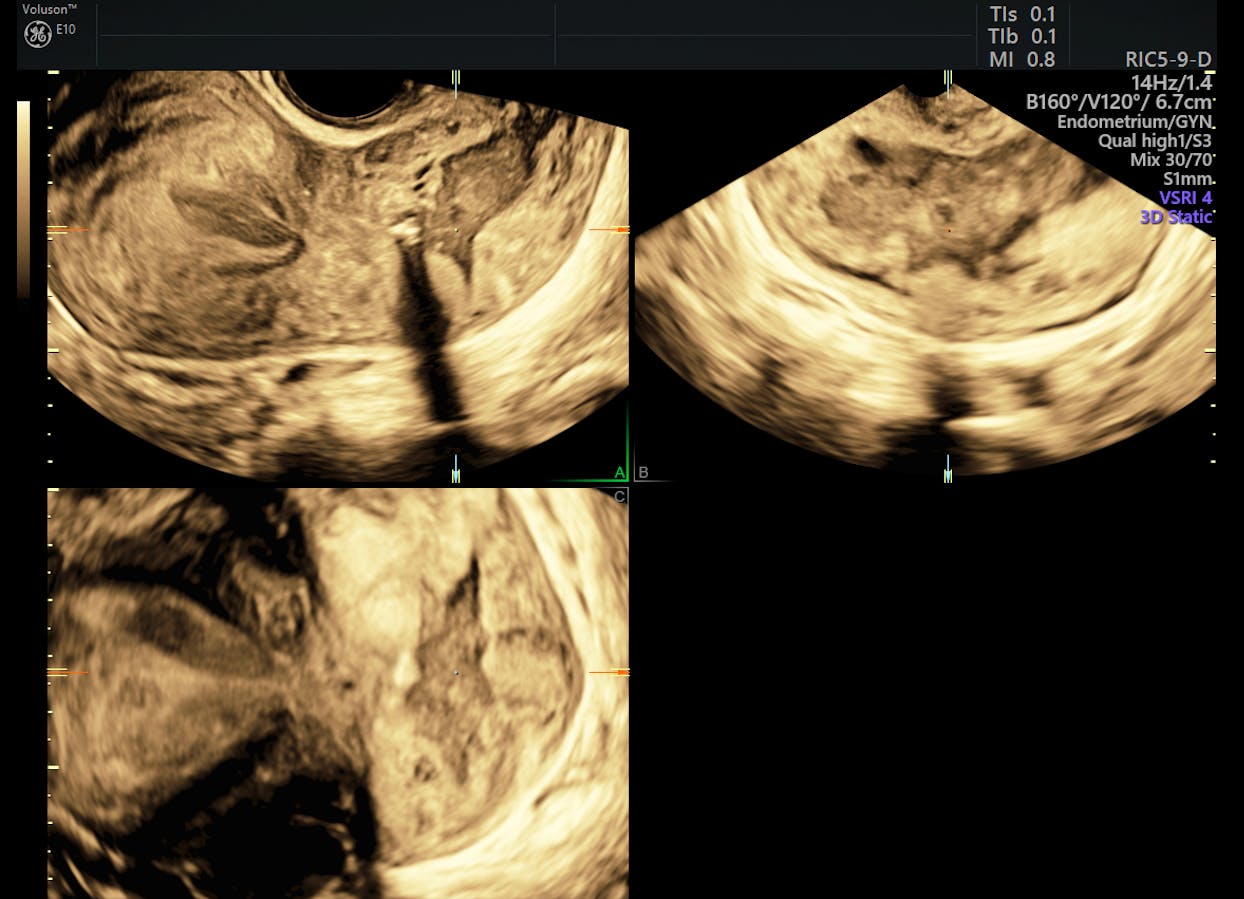

Ultrasound Of Patient S Neck Region Revealing Multiple Enlarged Lymph Download Scientific Diagram from www.researchgate.net If this happens, it is called metastasis. I had an ultrasound done in 2012 but the report for this scan never reached my previous doctor's practice and so nothing was. Ultrasound uses sound waves to create images of the body on a computer monitor. I have ocd and my obsession of 30 years is that i have a tumor on in my throat or neck. This study was done to evaluate the use of ultrasound to examine lymph nodes in the neck in surgical planning for thyroid cancer surgery and to identify which patients are best served. It can be used with a fine needle aspiration test or core biopsy test to accurately direct the tip of the needle into the lump. Some of the indications for thyroid or neck ultrasound are thyroid nodules, goiter, thyroid cancer and other neck masses. Expert ultrasound can also help confirm a diagnosis of papillary thyroid cancer which has spread to the lymph nodes of the neck.

Head and neck cancers include cancers in: There can be more than one sentinel node. I had an ultrasound done in 2012 but the report for this scan never reached my previous doctor's practice and so nothing was. This study was done to evaluate the use of ultrasound to examine lymph nodes in the neck in surgical planning for thyroid cancer surgery and to identify which patients are best served. An ultrasound of the thyroid produces pictures of the thyroid gland and the adjacent structures in the neck. While it can't diagnose cancer, it can detect the abnormal tissues that may possibly be cancerous. The image may or may not suggest cancer, but definitive diagnosis requires removal of. For most types of cancer, a biopsy is the only sure way for the doctor to know if an area of the body has cancer. When ultrasound is performed on a patient with nodular goiter, or a patient with a history of thyroid cancer, finding a prominent lymph node with a rounded shape (long/short axis ratio < 2) and absent hilar line warrants further evaluation of the node (figs. Ultrasounds have many limitations an ultrasound is not good enough for many aspects of cancer. Carotid ultrasound tests for blocked or narrowed carotid arteries, which can increase the. Confirming that a lump in the neck is developing from the thyroid or connected tissue. Spread of thyroid cancer to the lymph nodes in the neck is common and increases the risk of cancer recurrence.

Figure 3 From Post Thyroidectomy Neck Ultrasonography In Patients With Thyroid Cancer And A Review Of The Literature Semantic Scholar from d3i71xaburhd42.cloudfront.net Ultrasound is often one of the first line tests in the detection of cancer. These tests can also show whether a nodule is toxic or producing too much thyroxine, causing hyperthyroidism. Spread of thyroid cancer to the lymph nodes in the neck is common and increases the risk of cancer recurrence. I was officially diagnosed hashimoto's by my endocrinologist 2 weeks ago but she has refused to do an ultrasound of the thyroid. 8.4, 8.5, 8.6, 8.7, and 8.8). An ultrasound of the neck is used to examine the carotid arteries located on each side of a patient's neck. Our doctors also use ultrasound to check lymph nodes in the neck, where some forms of thyroid cancer can spread. It can be used with a fine needle aspiration test or core biopsy test to accurately direct the tip of the needle into the lump.

Carotid ultrasound tests for blocked or narrowed carotid arteries, which can increase the. Some of the indications for thyroid or neck ultrasound are thyroid nodules, goiter, thyroid cancer and other neck masses. Expert ultrasound can also help confirm a diagnosis of papillary thyroid cancer which has spread to the lymph nodes of the neck. It can detect abnormal tissues, growths, and cysts and give a suspicion of cancer based on how those images look. Ultrasound is widely available an is useful to identify abnormal lymph nodes that may contain cancer.

Ultrasonographic Differentiation Of Benign From Malignant Neck Lymphadenopathy In Thyroid Cancer Kuna 2006 Journal Of Ultrasound In Medicine Wiley Online Library from onlinelibrary.wiley.com But today, it is more common for a thyroid cancer to be incidentally identified on a ct/mri or neck ultrasound done for some reason unrelated to the thyroid. An ultrasound of the thyroid produces pictures of the thyroid gland and the adjacent structures in the neck. An ultrasound of the neck is used to examine the carotid arteries located on each side of a patient's neck. The mouth (oral cavity or oral cancers) the tongue. Doctors may also do tests to learn which treatments could work best. It can be used with a fine needle aspiration test or core biopsy test to accurately direct the tip of the needle into the lump. Ultrasound is relatively quick and simple test that gives very useful information about the soft tissues in the head and neck region including the lymph glands, salivary glands, thyroid gland and any abnormal lumps. The image of your thyroid and any nodules, even those you can't feel, will show up on a computer screen.

People may use the word throat to describe different parts of the neck. Your two carotid arteries are located on each side of your neck. A neck ultrasound can be used to observe the thyroid gland to look for nodules, growths, or tumors. Although many unskilled observers would believe that size is a major issue, but it actually is not. Lymph nodes are part of the lymphatic system, which helps to protect us from infection and disease. If this happens, it is called metastasis. Part of the throat (cancers of the oropharynx and tonsils, nasopharynx and hypopharynx) the nose or sinuses (nasal and sinus cancer) the salivary glands. If the person has a lump in the neck, an fna can show if the mass is from cancer spread. The expert ultrasonographer will look for multiple changes. While it can't diagnose cancer, it can detect the abnormal tissues that may possibly be cancerous. Ultrasound guidance is used to perform thyroid biopsies and improves the diagnostic accuracy of fine needle biopsy. If this lump is of concern then a biopsy would be the next step. An ultrasound of the neck is used to examine the carotid arteries located on each side of a patient's neck.